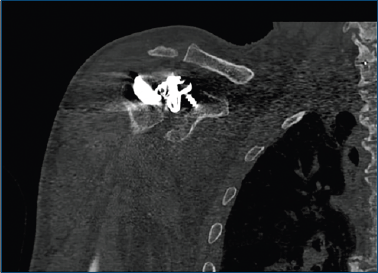

Intraoperatoriamente, è stata identificata una dislocazione supero-anteriore della glenosfera, insieme alla mobilizzazione della vite craniale del baseplate. Non vi erano segni di mobilizzazione dello stelo omerale o dell’inserto. Erano presenti esteso tessuto cicatriziale e metallosi periprotesica, con metallosi anche all’interno del connettore della glenosfera (Fig. 3).

Figura 3. Immagine intraoperatoria, metallosi periprotesica e tessuto cicatriziale. Il metal-back glenoideo è coperto e non visibile.